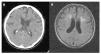

Protocolo de empleo e interpretación de pruebas de imagen y funcionales en el diagnóstico de las demencias